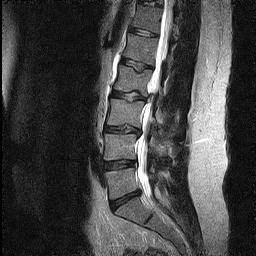

Within the Recovering Grace community, many often are confronted by well-meaning friends or family who believe that the spiritually wounded should just get over it. The refrains vary from, “You’re being bitter,” to “You just need to leave it at the cross,” to “You WANT to hang on to this.” I recently underwent lumbar spinal fusion surgery after six months of debilitating back pain and after more conservative measures failed to resolve the problem. While I’ve been recovering, it’s given me a lot of time to think and reflect on some parallels between physical and spiritual healing.

I ultimately saw a physician who ordered tests and prescribed still more conservative remedies. I went to physical therapy. I had cortisone steroid injections in my spine. But while I have a number of friends who have found tremendous relief with steroid injections, these treatments did not help me or resolve the issue for me.